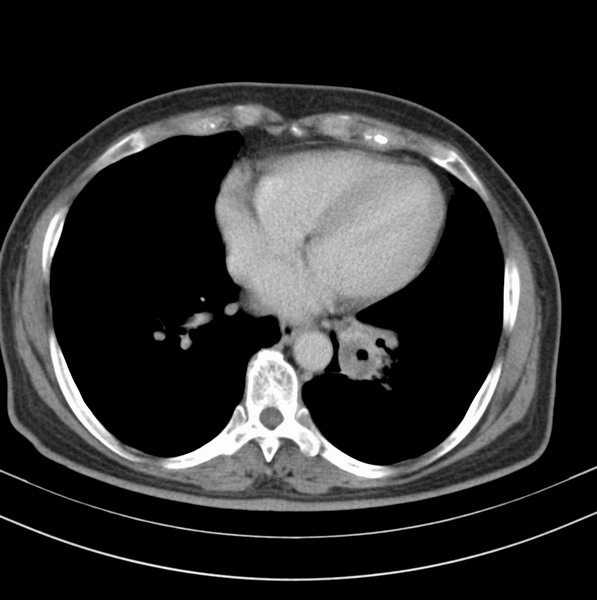

女、63

咳嗽、胸痛四个月

考虑左下肺中央型肺癌

支持左下中央型肺癌伴阻塞性炎症不张。

包绕左下肺基底段的不规则的软组织肿块,段支气管腔变形、狭窄及阻塞性炎症,病变区不规则强化,又是老年女性支持楼上看法。

典型病例:左下肺基底段中央型肺癌,相应支气管狭窄并阻塞性炎症